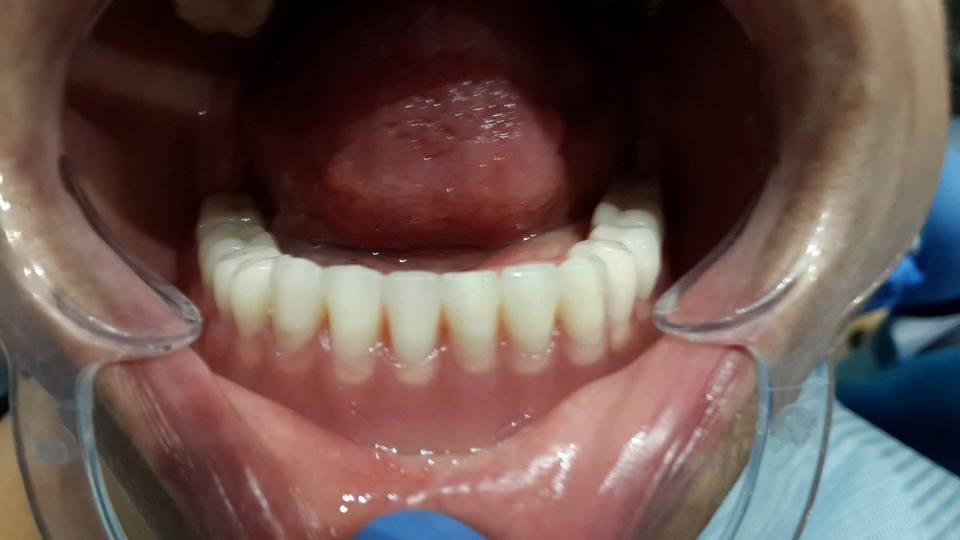

Prosthesis of the lower jaw on 4 implants

The patient was given a prosthetic lower jaw on 4 implants.